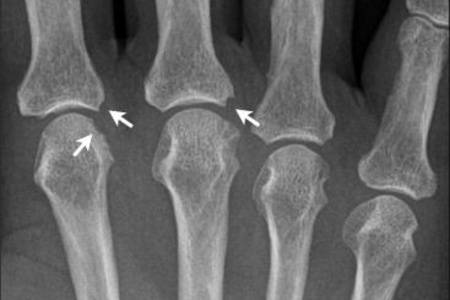

Вторая рентгенологическая стадия заболевания разделяется на две подгруппы, в зависимости от степени повреждений в виде эрозии суставной поверхности:

- подгруппа А второй рентгенологической стадии характеризуется отсутствием эрозий на суставных поверхностях, на снимке выявляют околосуставной остеопороз в виде кист (локальные просветления костных структур), участков костных уплотнений и более заметное сужение щели между суставными поверхностями;

- подгруппа Б второй рентгенологической стадии патологии помимо основных проявлений характеризуется появлением эрозий поверхностей суставов, не более, чем в четырёх местах.

Эрозии костей при патологии

Эрозии костных структур делят на три вида:

- Краевая или поверхностная — выявляется уже на второй стадии в суставах, где отсутствует хрящевая структура и трение более жёсткое.

- Компрессионная — происходит из-за усугубления процесса и провала кости в месте повреждения.

- Деформирующая — формируется из-за разрушения костной пластины, визуально наблюдается видимая деформация кости, характерна для 4 стадии патологии.